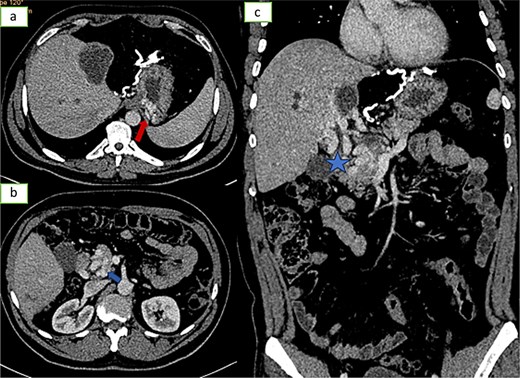

![Axial sections of an injected abdominopelvic CT scan [(a) arterial temp; (b) portal temp] and (c) coronal reconstruction showing portal hydatidosis with the presence of a cavernoma of the hepatic hilum.](https://oupdevcdn.silverchair-staging.com/oup/backfile/Content_public/Journal/jscr/2025/5/10.1093_jscr_rjaf337/1/m_rjaf337f3.jpeg?Expires=1770158113&Signature=dE16TbDi-pQcziK5ClFDeb5oXIlLY0EukDHXy9q7V9ASPG1sdfuKYKjlJayP~JDAtZ3gRE4mXdbVT8c8NAA2jB-Ju~unmeeLqiLKkxGEDjkHdLFBXDzWa2rTIDJiGQh6MXuKcNHlLIUtIBKegbLdzzt7fzetcU056YXEZxf63UOkns7EQEiKR95KV04msUyrpOKTna1qjb5WwQmwXvp0pOY5E6pmiDxLgyMEh3MKi8lr-5cIIo2ZjPjBnN4r8XoL4RUh1DfPAnm3Vx6cRWpHuBdn0WwGRJk8-rs49j15nIgjqUyKvogx9-X4IMAyM1Zog7Gde7Rz16o1l1uMnkg8qQ__&Key-Pair-Id=APKAIYYTVHKX7JZB5EAA)

Axial sections of an injected abdominopelvic CT scan [(a) arterial temp; (b) portal temp] and (c) coronal reconstruction showing portal hydatidosis with the presence of a cavernoma of the hepatic hilum.